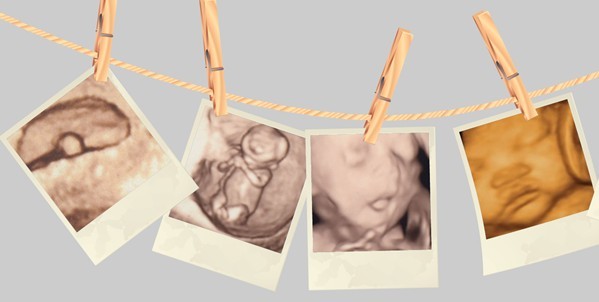

优势三:有纪念意义

GE四维彩超能够对胎儿拍摄宫内写真,为孕期增添了不少情趣,孕妈咪可以亲眼目睹宝宝的秀荣和乖巧的动作,并将这些动作拍摄下来或者录制成光碟,为孕期留下美好的回忆。